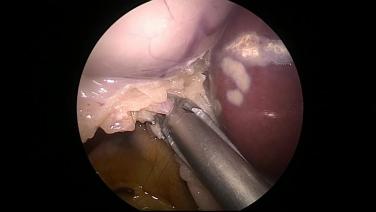

Laparoscopic Cholecystectomy - Identify & Ligate Cystic Artery

Laparoscopic Cholecystectomy - Identify & Ligate Cystic Duct

Laparoscopic Cholecystectomy - Transect Cystic Duct & Artery